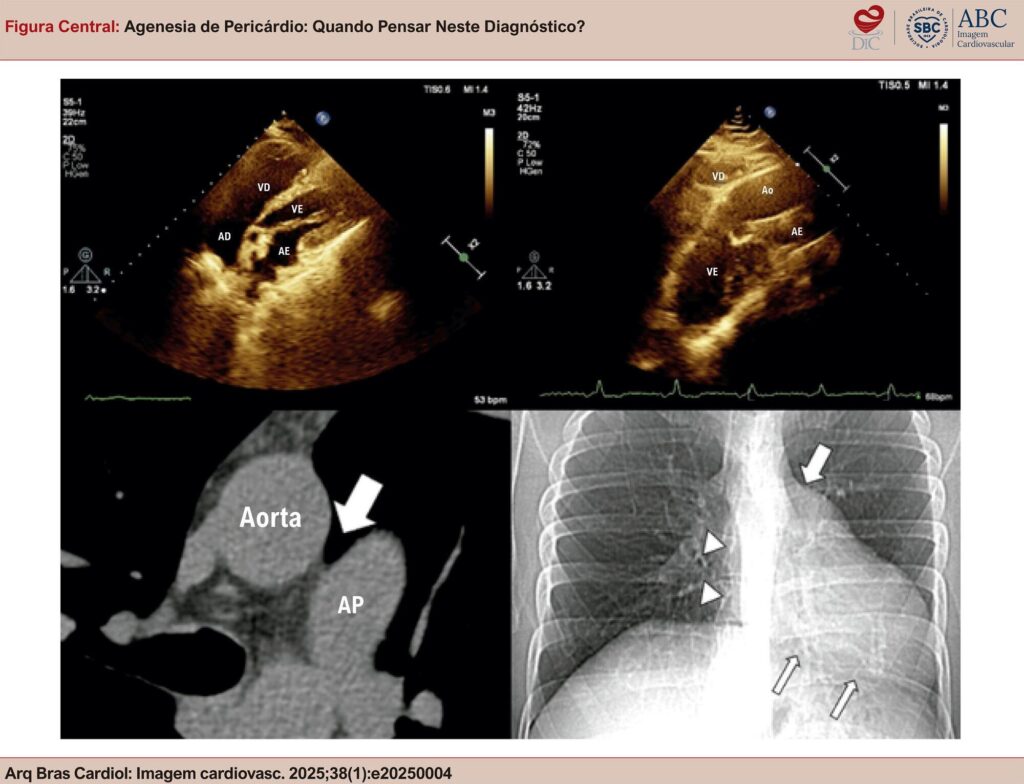

Figura Central

: Agenesia de Pericárdio: Quando Pensar Neste Diagnóstico?